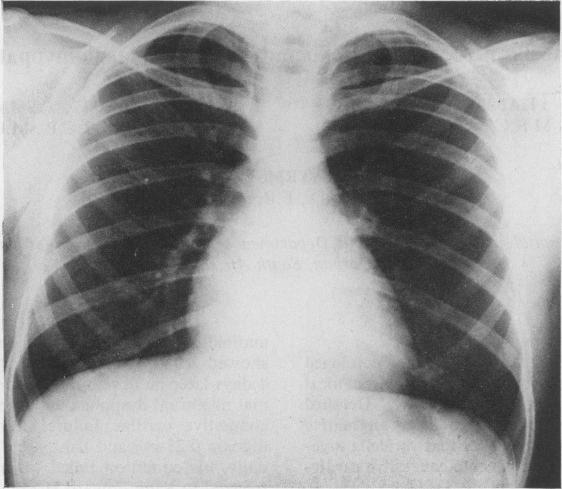

A 14-year-old boy with proved varicella developed severe, intractable heart failure with the clinical features of congestive cardiomyopathy. Detailed investigations failed to disclose any alternative aetiological factor. It is proposed that varicella myocarditis was the cause of the acute congestive cardiomyopathy found in this patient.

Varicella myocarditis producing congestive cardiomyopathy.